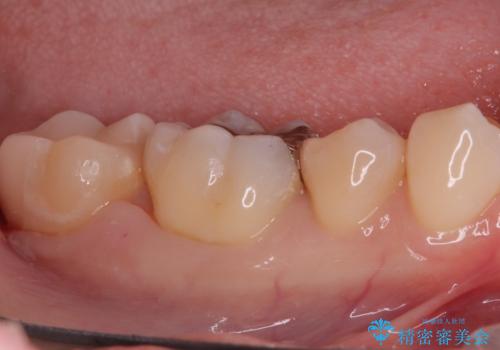

奥歯の銀歯を自然に!右下6番のメタルフリー治療

- 右下6番の奥歯に入っている金属の詰め物(メタルインレー)を気にされてご来院されました。お口の中の金属をなくしたいという患者様のご希望と、見た目の改善を目指し、天然歯に近い色と質感を持つセラミックインレーに交換する治療計画を立案しました。これにより、審美性の向上と、金属アレルギーのリスクがないメタルフリーの環境を実現することを目指しました。

治療では、まず古い金属のインレーを慎重に取り外し、内部に虫歯の再発がないかを丁寧に確認しました。歯を最小限だけ形成した後、精密な型取りから患者様の歯の色に合わせたオーダーメイドのセラミックインレーを作製しました。セラミックは、歯質との適合性が高く、プラークが付着しにくいため、虫歯の再発リスクを抑えるメリットもあります。適合性の高いセラミックインレーを装着することで、長年のコンプレックスだった銀歯がなくなり、機能的にも安定した自然な奥歯を取り戻していただけました。